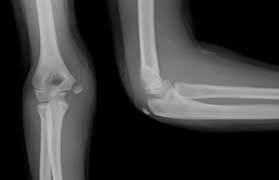

Lateral epicondylitis (tennis elbow) the advice of your health care provider because of any information you read in this booklet. Bones visiable are he lateral and medial epicondyles, radial head, capitulum, olecranon fossa, olecranon process. Pain upon resisted wrist extension. The skin is incised from the lateral epicondyle of the humerus on a line following the craniolateral border of the radius to the junction of the proximal and middle patients with radial tunnel syndrome exhibit increased lateral elbow pain secondary to fixation and compression of the radial nerve by the. Resisted wrist extension with elbow fully extended.

The Radiology Assistant Fractures In Children

The Radiology Assistant Fractures In Children from radiologyassistant.nl

Tennis is not the only cause of this condition, but tennis players do get the condition usually as a result of overuse of the muscles/tendons that they use to hit a backhand shot. Few mm distal to tip of lateral epicondyle. The following maneuvers exacerbate pain at lateral epicondyle. The medial and lateral epicondyles are small bony tuberosities on the distal end of the humerus (fig. Extensor carpi radialis brevis muscle. Performed with the elbow extended. The lateral epicondyle of the humerus is a large, tuberculated eminence, curved a little forward, and giving attachment to the radial collateral ligament of the elbow joint, and to a tendon common to the origin of the supinator and some of the extensor muscles. Patient is seated facing table, leaning laterally and rotating shoulder externally so that post.